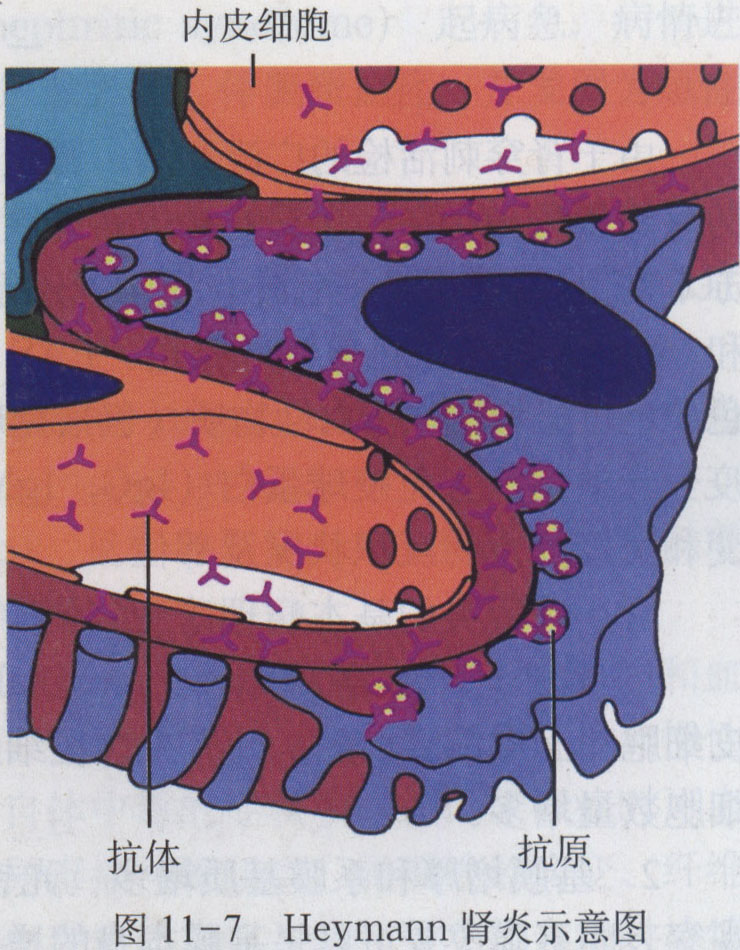

8 泌尿系统疾病

8.4 素材资源